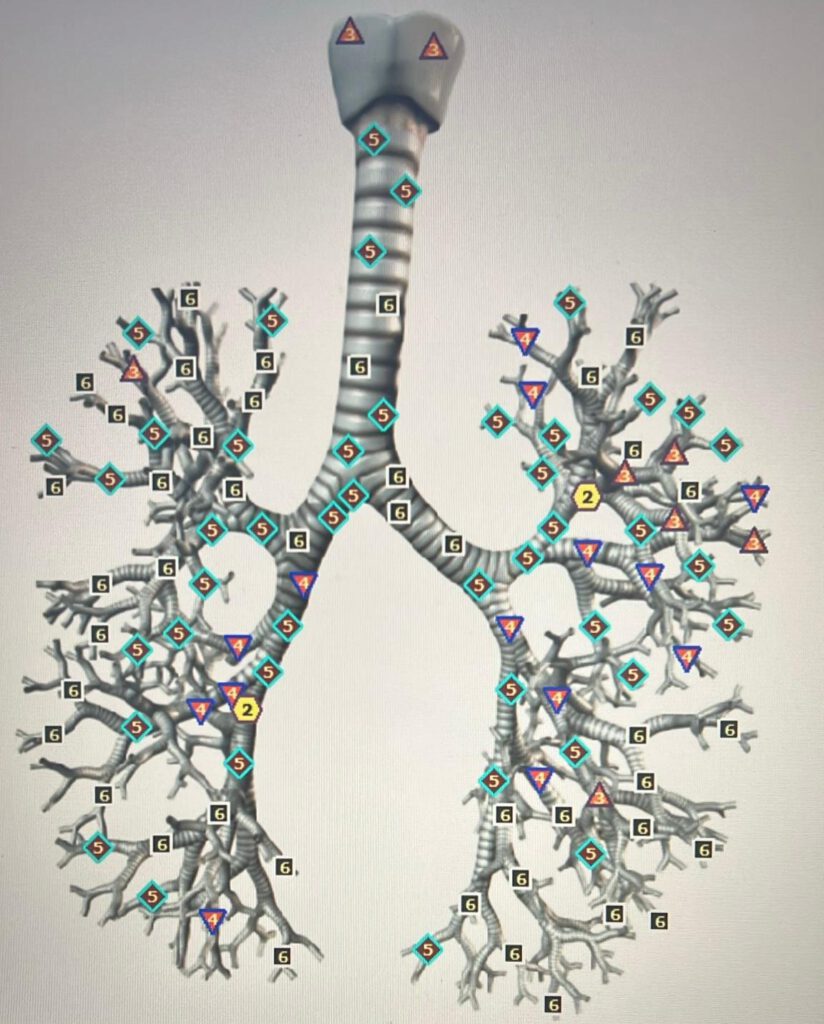

Hier links op de afbeelding zie je de luchtpijp en bronchiën zonder bacterie, dus hoe deze nu in originele staat zijn.

Je ziet hier dus al een aantal behoorlijke verzwakkingen.

Je ziet dit aan de grote hoeveelheid zesjes en vijven, maar ook behoorlijk wat vieren.

De tweeën en drieën die je ziet, zijn uiteraard wel goed!